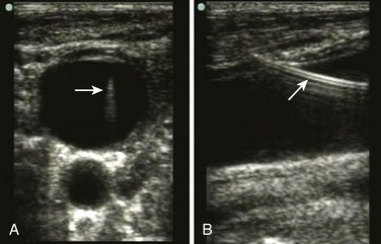

- Pressure measurement has been shown to be effective to prevent arterial cannulation.2 Take the small angiocatheter provided in kit and slide it over th

e wire. Remove the wire. Use the sterile IV extension tubing, and fill it with saline. Attach IV tubing to the angiocatheter, and hold the IV tubing vertically. If the column of saline falls down into the patient, this confirms venous placement. If arterial, the blood will be pulsatile rise up the tubing (see image). - Transduce a CVP with the help of the bedside nurse. This also requires placement of angiocatheter over the guidewire, and then attaching a digital transducer to the angiocatheter.